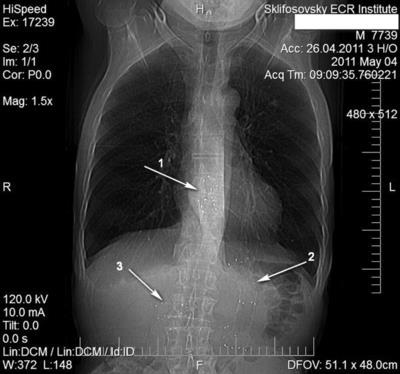

Beteg H .. 54 éves, a közös vállalat hajtottuk 3/19/13 Indiában egy nap után spontán törés (Boerhaave szindróma). 29.03 ugyanabban az évben mintegy empyema bal mellkas végeztünk vele, pleurectomy, hántoláson a tüdő. 04/15/13 egy moszkvai kórházban megállapították, hogy a stent vándorolt a gyomor és a beteg úgy tartja ezofagomediastinoplevralnogo sipoly kiújulás és tagolt baloldali mellkasi empyemára. 04/22/13 SRI mentő végre Laparotomiát diafragmotomiya vesznek fel hiba nyelőcső, Nissen LF, gastrostomán a Kader eltávolítása, valamint a stent, thoracostomy. A műtét után végeztük aspirációs-öblítő kezelés empyemára. Vissza.